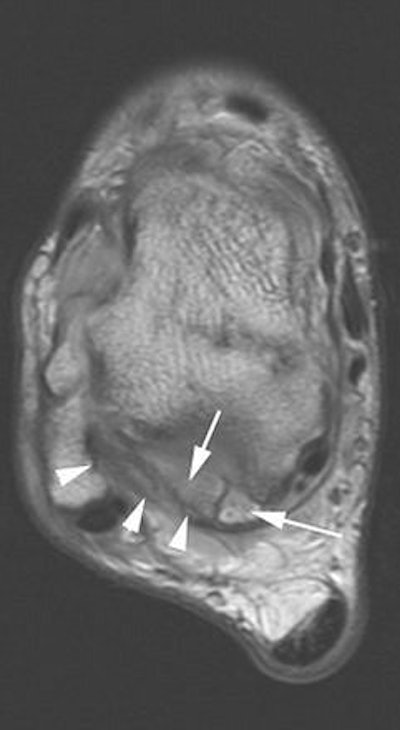

On the MRI exams in the U.K. study, Dr. Philip Robinson from Leeds Teaching Hospitals at St. James University Hospital in Leeds found a preponderance of posterolateral synovitis, thickened posterior talofibular ligaments, and a lack of FHL tenosynovitis

In a study published earlier this year by Robinson, the MR sequence consisted of axial proton density-weighted, sagittal T1-weighted conventional spin-echo imaging; axial, sagittal, and coronal T2-weighted conventional spin-echo fat-suppressed imaging; and gadolinium-enhanced axial and sagittal T1-weighted conventional spin-echo fat-suppressed imaging.

These exams were conducted in a patient population of nine athletes imaged on a 1.5-tesla scanner (Intera, Philips Medical Systems, Andover, MA). On imaging, the posterior ankle was evaluated for synovitis in the posteromedial, posterior, and posterolateral areas.

MR findings included posteromedial capsular thickening, tendon displacement, and posteromedial synovitis in all athletes with posteromedial impingement. Also, all posterolateral athletes had moderate to severe posterolateral synovitis. Bone marrow edema was prevent, but without specific distribution (Skeletal Radiology, February 2006, Vol. 35:2, pp. 88-94).

The focus of Robinson's most recent study, conducted with Dr. Steve Bollen from Bradford Royal Infirmary in Bradford, UK., was sonographically guided injection therapy. "We believe MRI should always be performed before injection to prevent subsequent masking of significant concomitant osteochondral or ligamentous injury," they wrote. "Our study results show a role for sonographically guided steroid and anesthetic injection into the posterolateral capsule abnormality" (American Journal of Roentgenology, July 2006, Vol. 187, pp. W53-W58).

For this retrospective study, they included 10 professional soccer players who had sustained an inversion injury of the ankle in the neutral position. Posterior impingement then developed.

All the players had undergone physical rehabilitation but still developed posterior pain. Both noncontrast and contrast-enhanced MR imaging was done. Ultrasound exams were performed with a 10-15 MHz transducer (Antares, Siemens Medical Solutions, Malvern, PA; ATL 5000, Philips Medical Systems) to evaluate the posterior capsule tissues including a Doppler study of soft-tissue abnormality.

| A 30-year-old male soccer player with clinical posterior impingement. Sagittal T2-weighted fat-suppressed MR image (TR/TE, 3,242/90; echo-train length, 9) shows os trigonum (lower arrow), joint effusion, and nodular posterolateral synovitis (arrowheads) between os trigonum and edematous posterior tibia (upper arrow). |